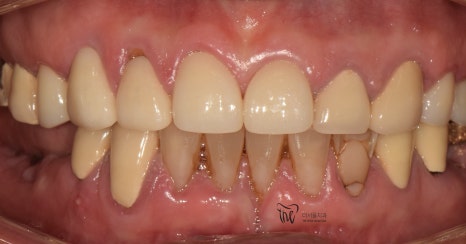

정면에서 봤을 땐, 비심미적인 모습을 보여주며

곳곳에 치경부파절증의 증세들이 드러나고

있습니다. 따라서 ,식사를 하실 때 마다

지끈거리는 통증 및 이가 시린 느낌을 지속적으로

받아오셨다 말씀을 하셨었죠.